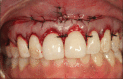

The containment of the elevator muscle of the upper lip and wing of nose was used for the treatment of patients with gummy smile. This technique had corrected esthetic alterations of smile, reducing the upper lip elevation, which results in a smaller gingival display. An upper lip lengthening as well as a reduction in the upper lip shortening when the patient smiled could be observed. The high smile line was corrected without compromising the labial harmony. This study presents an innovative and effective therapeutic option to obtain a natural and harmonious smile. The patient expressed a high degree of satisfaction.